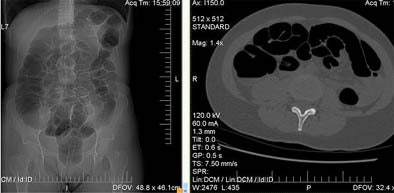

| A 65-year-old woman underwent follow-up VC following a right colectomy for colon cancer. The intervention three years earlier included removal of the ileocecal valve with subsequent ileocolic anastomosis. Insufflation in the supine decubitus did not cause abdominal pain. At VC the colon was normal but shows overdistension of the small bowel in the supine CT data (above) and confirmed in the prone CT data (below). Objective or subjective symptoms were not reported. Immediately after prone decubitus positioning, at the end of the exam, the patient reported headache, nausea, and stimulus to vomiting. Cold sweat and diaphoresis were also observed. All images courtesy of Dr. Emanuele Neri. |